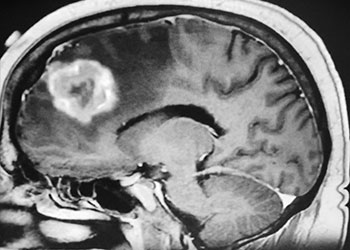

Brain:

Atypical Convexity Meningioma

Author: Jonathan L. Brisman M.D., F.A.C.S., Read More!